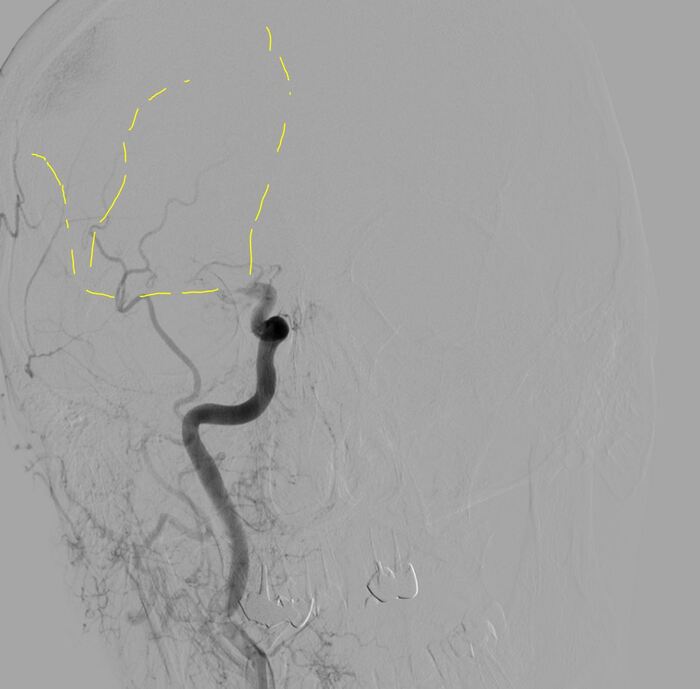

Далее делаю аспирацию с ретривером, дважды - минимальный прогресс, удалось только немного открыть ВСА:

Результат после двух попыток...